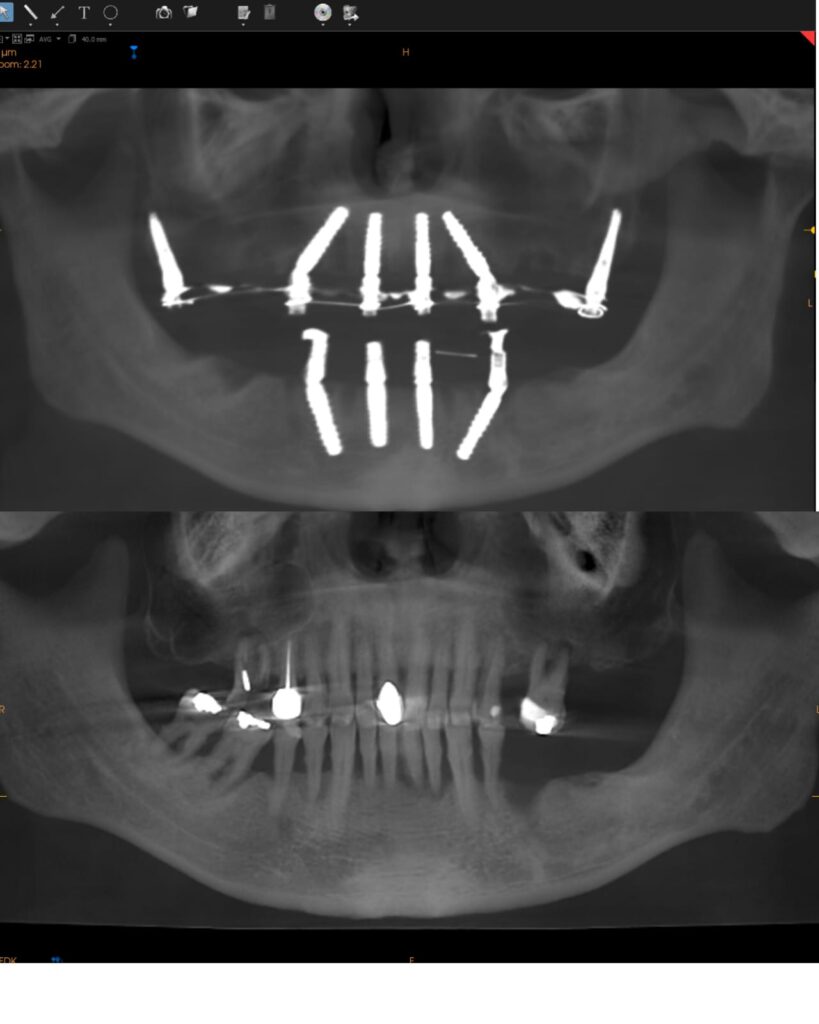

Send your panoramic X-rays or CBCT scan for initial evaluation. Our

implantologists will provide a customized plan, outline your treatment

schedule, and assist with travel planning. We can also schedule a Zoom

consultation with one of our specialists.

2. Clinical Evaluation & Surgical Planning

Upon arrival, a full exam and CBCT scan confirm your candidacy. Your procedure is

digitally guided for precise placement using the PIC system and surgical simulation.